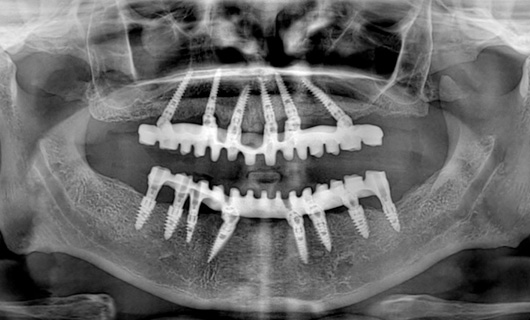

After placing dental implants, your dentist will fabricate dentures in the following steps:

- Impressions: After your gums are substantially healed and healthy, your dental assistant or dentist will make an impression of jaws.

- Modeling prosthesis: Your dentist will make a wax model of the dentures before fabricating the final product to check for fit and appearance. Modifications will be done at this stage to match the patient’s expectations regarding teeth size, shape, and color.

- Fabrication of final denture: Once you and your dentist have decided on a final fit and appearance, a dental technician or prosthodontist will construct a final prosthesis that is durable and natural-looking.

- Insertion: Once your final dentures are made, they are fixed to dental implants in the jaw bone.